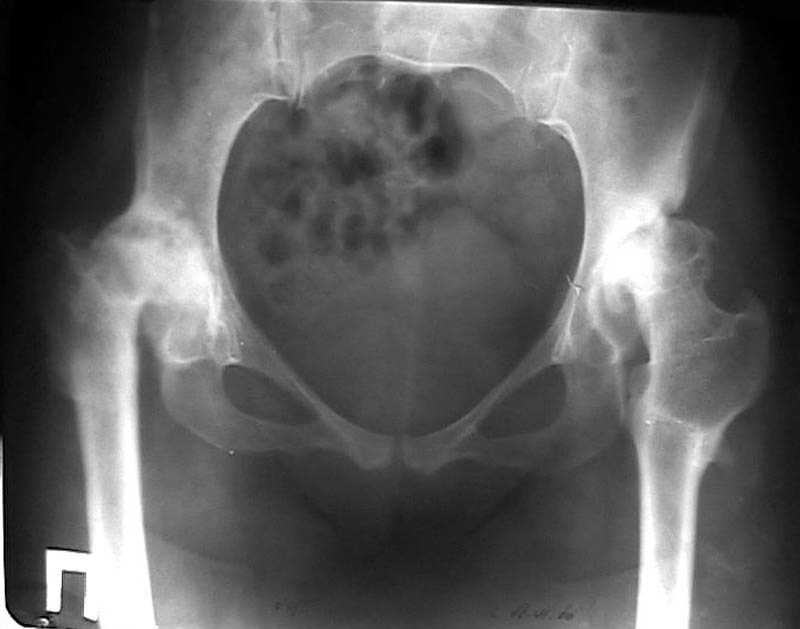

Мужчина, 38 лет. Двусторонний диспластический коксартрз, кифосколиоз.Правый сустав прооперирован 12.12.00, левый - в апреле 2003 г. Справа вывихнулась <чашка>.

Предполагается заменить <чашку>, наростив крышу <тутопластом>? Возможно ли использовать бесцементную <чашку>? Мнения? Заранее благодарю! С уважением,А.В.Владзимирский

На мой взгляд, оптимальным вариантом может быть использование антипротрузионой сетки и цементной чашки. Пластика крыши с учётом величины дефекта - любым материалом на Ваше усмотрение (ауто-, алло-)

Использовать бесцементную чашку я бы не рискнула.